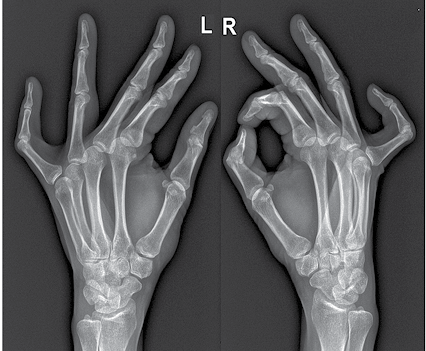

2024 m. liepos mėn. į Vilniaus universitetinę ligoninę Santaros klinikas kreipėsi moteris dėl penktojo piršto tirpimo ir deformacijos. Apžiūros metu pastebėta penktojo piršto PIP sąnario kontraktūra abiejose plaštakose. Nustatyta, kad dešinės rankos penktojo piršto PIP sąnario aktyvus tiesimas ribotas iki 75° kampo, naudojant jėgą pirštas ištiesiamas iki 50°. Kairės rankos atitinkami rezultatai – 40° ir 20°. Kiti pirštai ir sąnariai nepakitę. Pacientė gali sugniaužti kumštį.

6 pav. Pacientės plaštakos iš priekio

7 pav. Pacientės plaštakų rentgeno nuotrauka